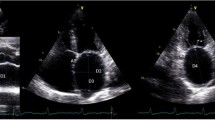

Nonvalvular atrial fibrillation (AF) is the most common sustained cardiac dysrhythmia and the most frequent cause of cardio-embolic stroke [1]. It is well known that left atrial appendage thrombi (LAAT) are the source of most embolic strokes in patients with nonvalvular AF [2, 3]. It is, likewise, widely accepted that transesophageal echocardiography (TEE) can identify LAAT and left atrial blood stasis, manifesting as spontaneous echo contrast (SEC), a known precursor of LAAT and systemic thromboembolism (Figure 1) [4–6].

All TTEs were reviewed offline by a board-certified (NBE) echocardiographer who was blinded to TEE and clinical data (HG). The mitral inflow early-diastolic pulsed-wave Doppler velocity (E) and the lateral mitral annulus tissue Doppler early-diastolic velocity (e’) were measured (cm/sec) and the E:e’ ratio was calculated (Figure 1). We did not analyze e’ velocities sampled from the medial mitral annulus, since this was not routinely obtained according to our laboratory protocol at the time when the study TTEs were performed (2005–2009). The Doppler measurements were obtained by averaging data from 3–5 consecutive beats. The left ventricular septal and posterior wall thicknesses and end-diastolic as well as end-systolic internal dimensions were measured from 2-dimentional and M-mode TTE images [13]. The left ventricular mass was calculated using the Devereux formula [14]. The left ventricular systolic and diastolic volumes and LVEF were measured using the biplane Simpson’s method or the Teichholz formula only when the former was not feasible due to suboptimal apical views [13, 15]. The left atrial dimensions (antero-posterior, medio-lateral and supero-inferior) were measured and the left atrial volume was calculated using the formula [4/3π (D1/2) (D2/2) (D3/2)] where each “D” represents one of three atrial dimensions [13]. All volume and mass measurements were indexed to the body surface area. The heart rhythm during TTE acquisition was determined from examination of the rhythm strip on the screen display.